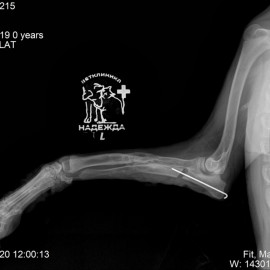

Собака по кличке Айза из города Ухта. Обратились в клинику с жалобами на сохраняющуюся хромоту на левую грудную конечность после полученных повреждений за 2 месяца до обращения к нам. После проведения осмотра и рентгенологического исследования было установлено: визуализируется костная мозоль в области средней трети диафиза левой лучевой и локтевой кости, левый локтевой сустава неконгруэнтный, деформаций локтевой кости по длине. Поставлен диагноз - анкилоз левого локтевого сустава, состояние после МОС левого предплечья, сросшийся перелом левой лучевой и локтевой кости. Была проведена операция - проксимальная динамическая остеотомия левой локтевой кости.

Снимок 1-2 до операции.